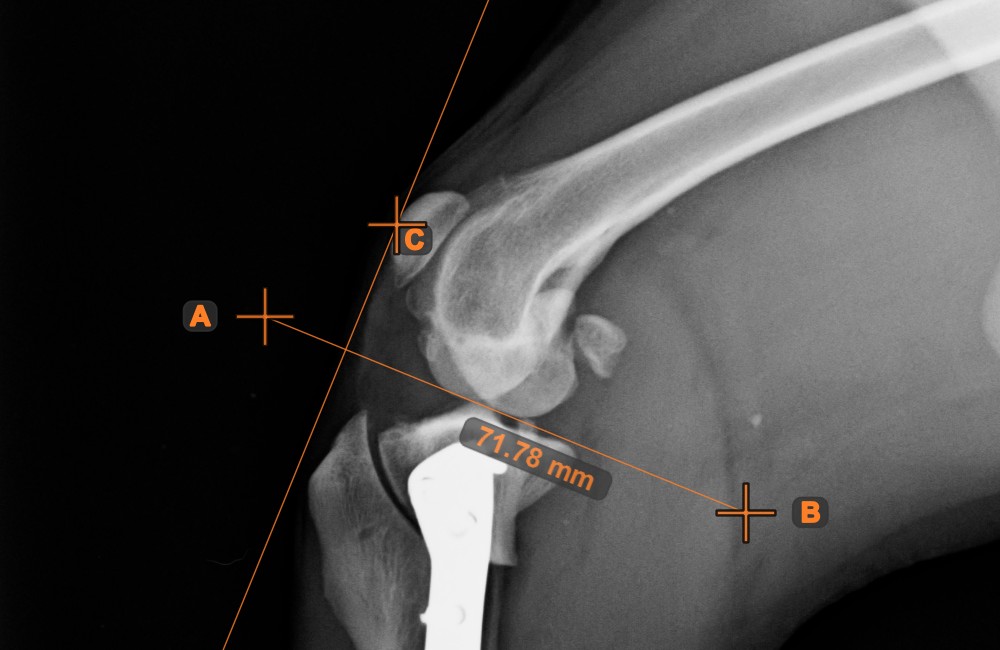

Line Intersection

Quickly and accurately locate and mark the intersection point between two existing lines by using the Line Intersection tool.

Select the tool from the left toolbar and assign it to one of the available mouse buttons. Select two lines that have already been drawn on the scene to complete the measurement. The intersection point of the line will be automatically calculated and marked on the scene. The intersection point of two lines will always be marked with the letter X.

Information

If two lines do not intersect directly, the intersection point of their extended projections on the scene will be marked.

../_images/image408.jpg ../_images/image37.jpg